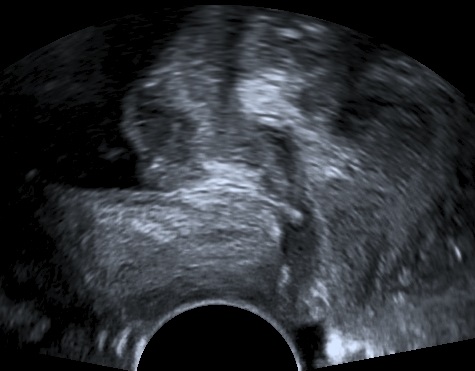

An 80-year-old female patient presents with persisting overactive bladder symptoms. After careful ultrasound examination, a unilocular cystic mass with a single urethral connecting tract containing a calculus was identified as an urethral diverticulum.

The clinician’s suspicion after acquiring a thorough patient’s history should lead to a targetted ultrasound examination combined with digital compression for possible excretion of fluid. The diagnostics may be completed with cystourethroscopy, micturating cystourethrogram, or MRI.